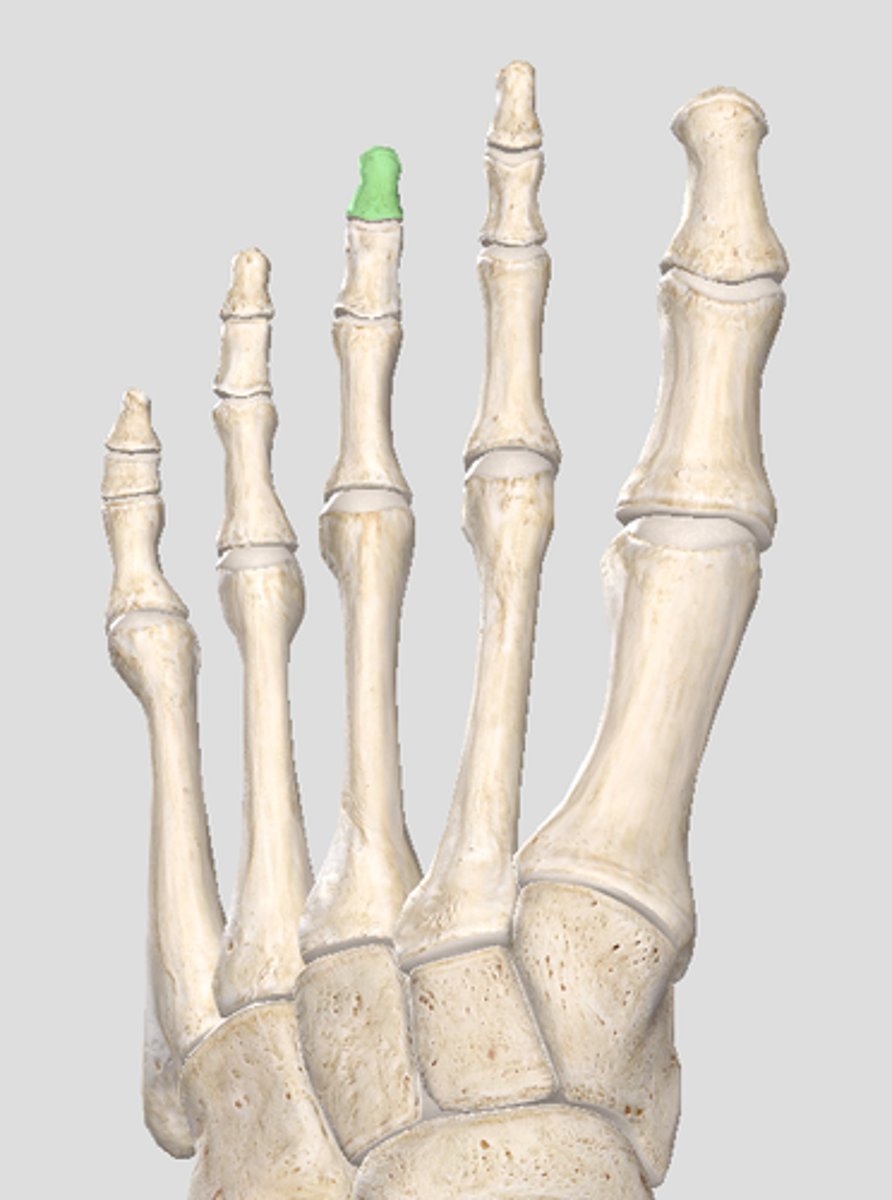

Proximal phalanx of digit 3